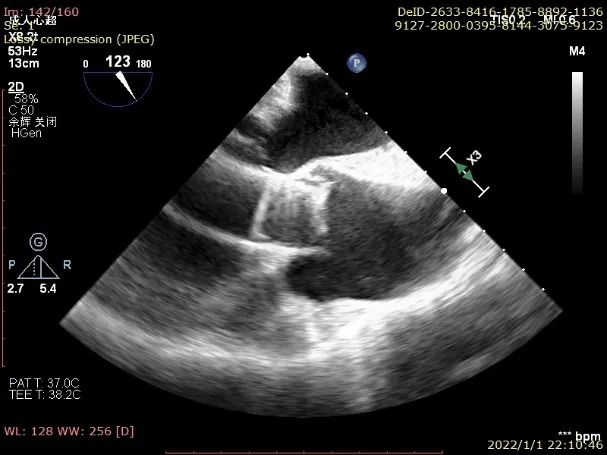

超声:

1. 升主动脉扩张,主动脉窦部内径4.3cm,窦管交界近消失,内径5.1cm,主动脉瓣三瓣瓣缘回声钙化、粘连,开放不佳,CW:收缩期主动脉瓣口最大血流速度:3.1cm/s,最大压差:38mmHg,平均压差:19mmHg,主动脉瓣环径2.7cm,主动脉瓣弓部内径3.5cm。肺动脉增宽。肺动脉瓣形态、活动正常;

2. 左心扩大,右心不大;

3. 二尖瓣刑天、开放可,闭合欠佳;三尖瓣形态、开放可,闭合欠佳;

4. 室间隔增厚,左室后壁增厚,二者呈逆向运动,未见节段性室壁运动异常;

5. 房、室间隔未见连续中断;

6. CDFI:主动脉半口舒张期可见大量反流信号。

超声提示:

升主动脉扩张;

主动脉瓣钙化、轻度狭窄并重度关闭不全;

左心扩大、左室壁增厚;

二尖瓣轻度关闭不全、三尖瓣轻中度关闭不全;

肺动脉增宽。

TEE示主动脉瓣大量反流

TEE提示定位件准确入窦

TEE提示瓣膜形态、位置良好

DSA(左)及TEE(右)提示无瓣周漏